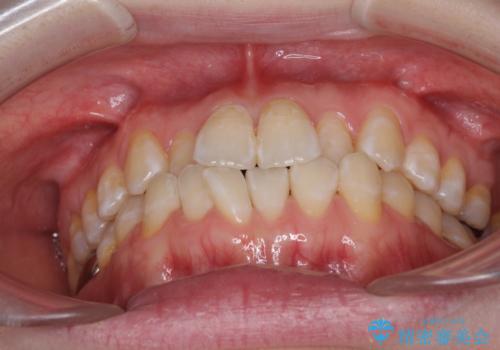

前歯のデコボコを治したい インビザラインによる矯正治療

- 前歯のデコボコを治したいとのことで来院された患者様です。

上下顎ともに歯列全体の後方移動とIPR(歯と歯の間を削る)によってデコボコが解消するように設計し、インビザラインにより治療を行うこととしました。

1日22時間の装着時間をほとんど達成することができず、治療には当初予定の2倍以上の期間を要することとなりました。